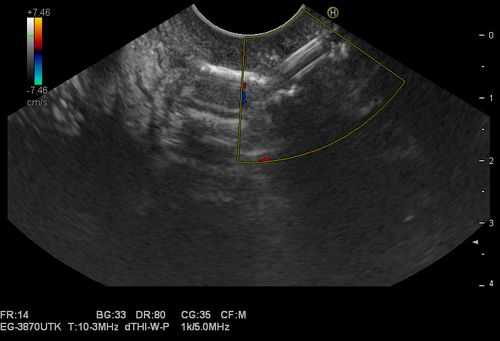

1. Проведение в желудок эхоэндоскопа OlympusGF-UE 160 и эндоскопическое ультразвуковое сканирование органов брюшной полости для определения зоны контакта стенки кисты со стенкой желудка (рис. 1). Рис. 1. Эхоэндоскопия и ультразвуковая визуализация панкреатической псевдокисты в теле поджелудочной железы (случай 1).

ПК локализовались в теле ПЖ у 7 (30,4%) пациентов, в хвосте ПЖ — у 7 (30,4%), в головке ПЖ — у 6 (26,2%) (рис. 1). Рис. 1. Псевдокиста головки поджелудочной железы (изображение при ультразвуковом исследовании). Стрелками указаны полость псевдокисты (1), бессосудистая зона (2). The arrows indicate pseudocyst cavity (1), avascular zone (2). У 3 (1%) больных имело место сочетанное расположение ПК в головке и теле ПЖ.